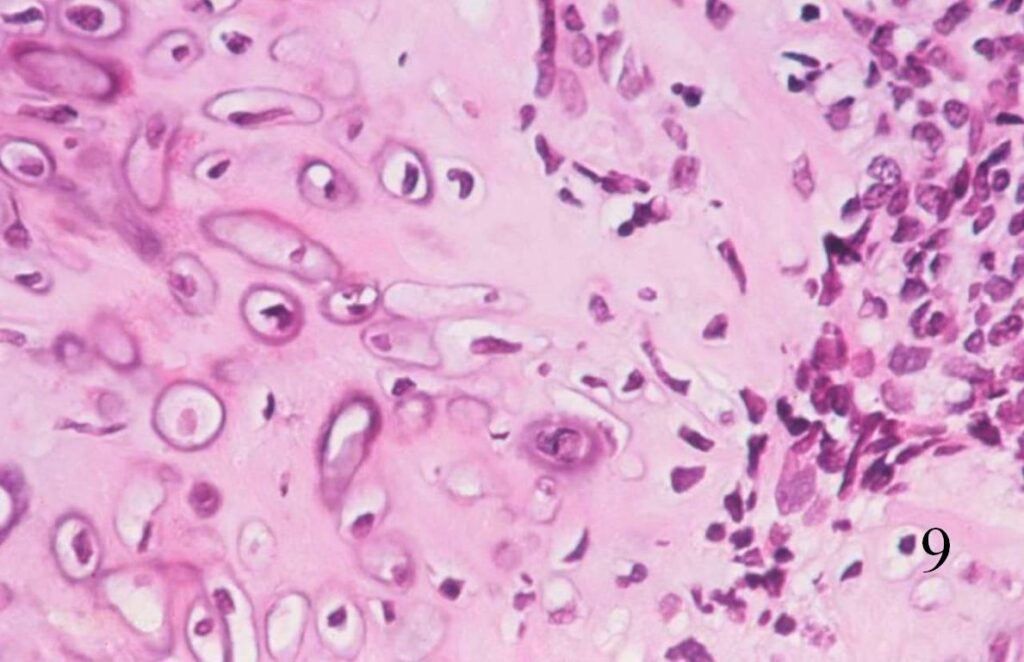

Fig. 8

Fig. 9

Fig. 10

Fig. 8-10 Low (Fig. 8) and high power (Fig. 9) magnification of a mesenchymal chondrosarcoma shows cartilaginous areas and a mesenchymal component.

Fig. 10. High power magnification of mesenchymal area shows an area of undifferentiated small round blue cells.